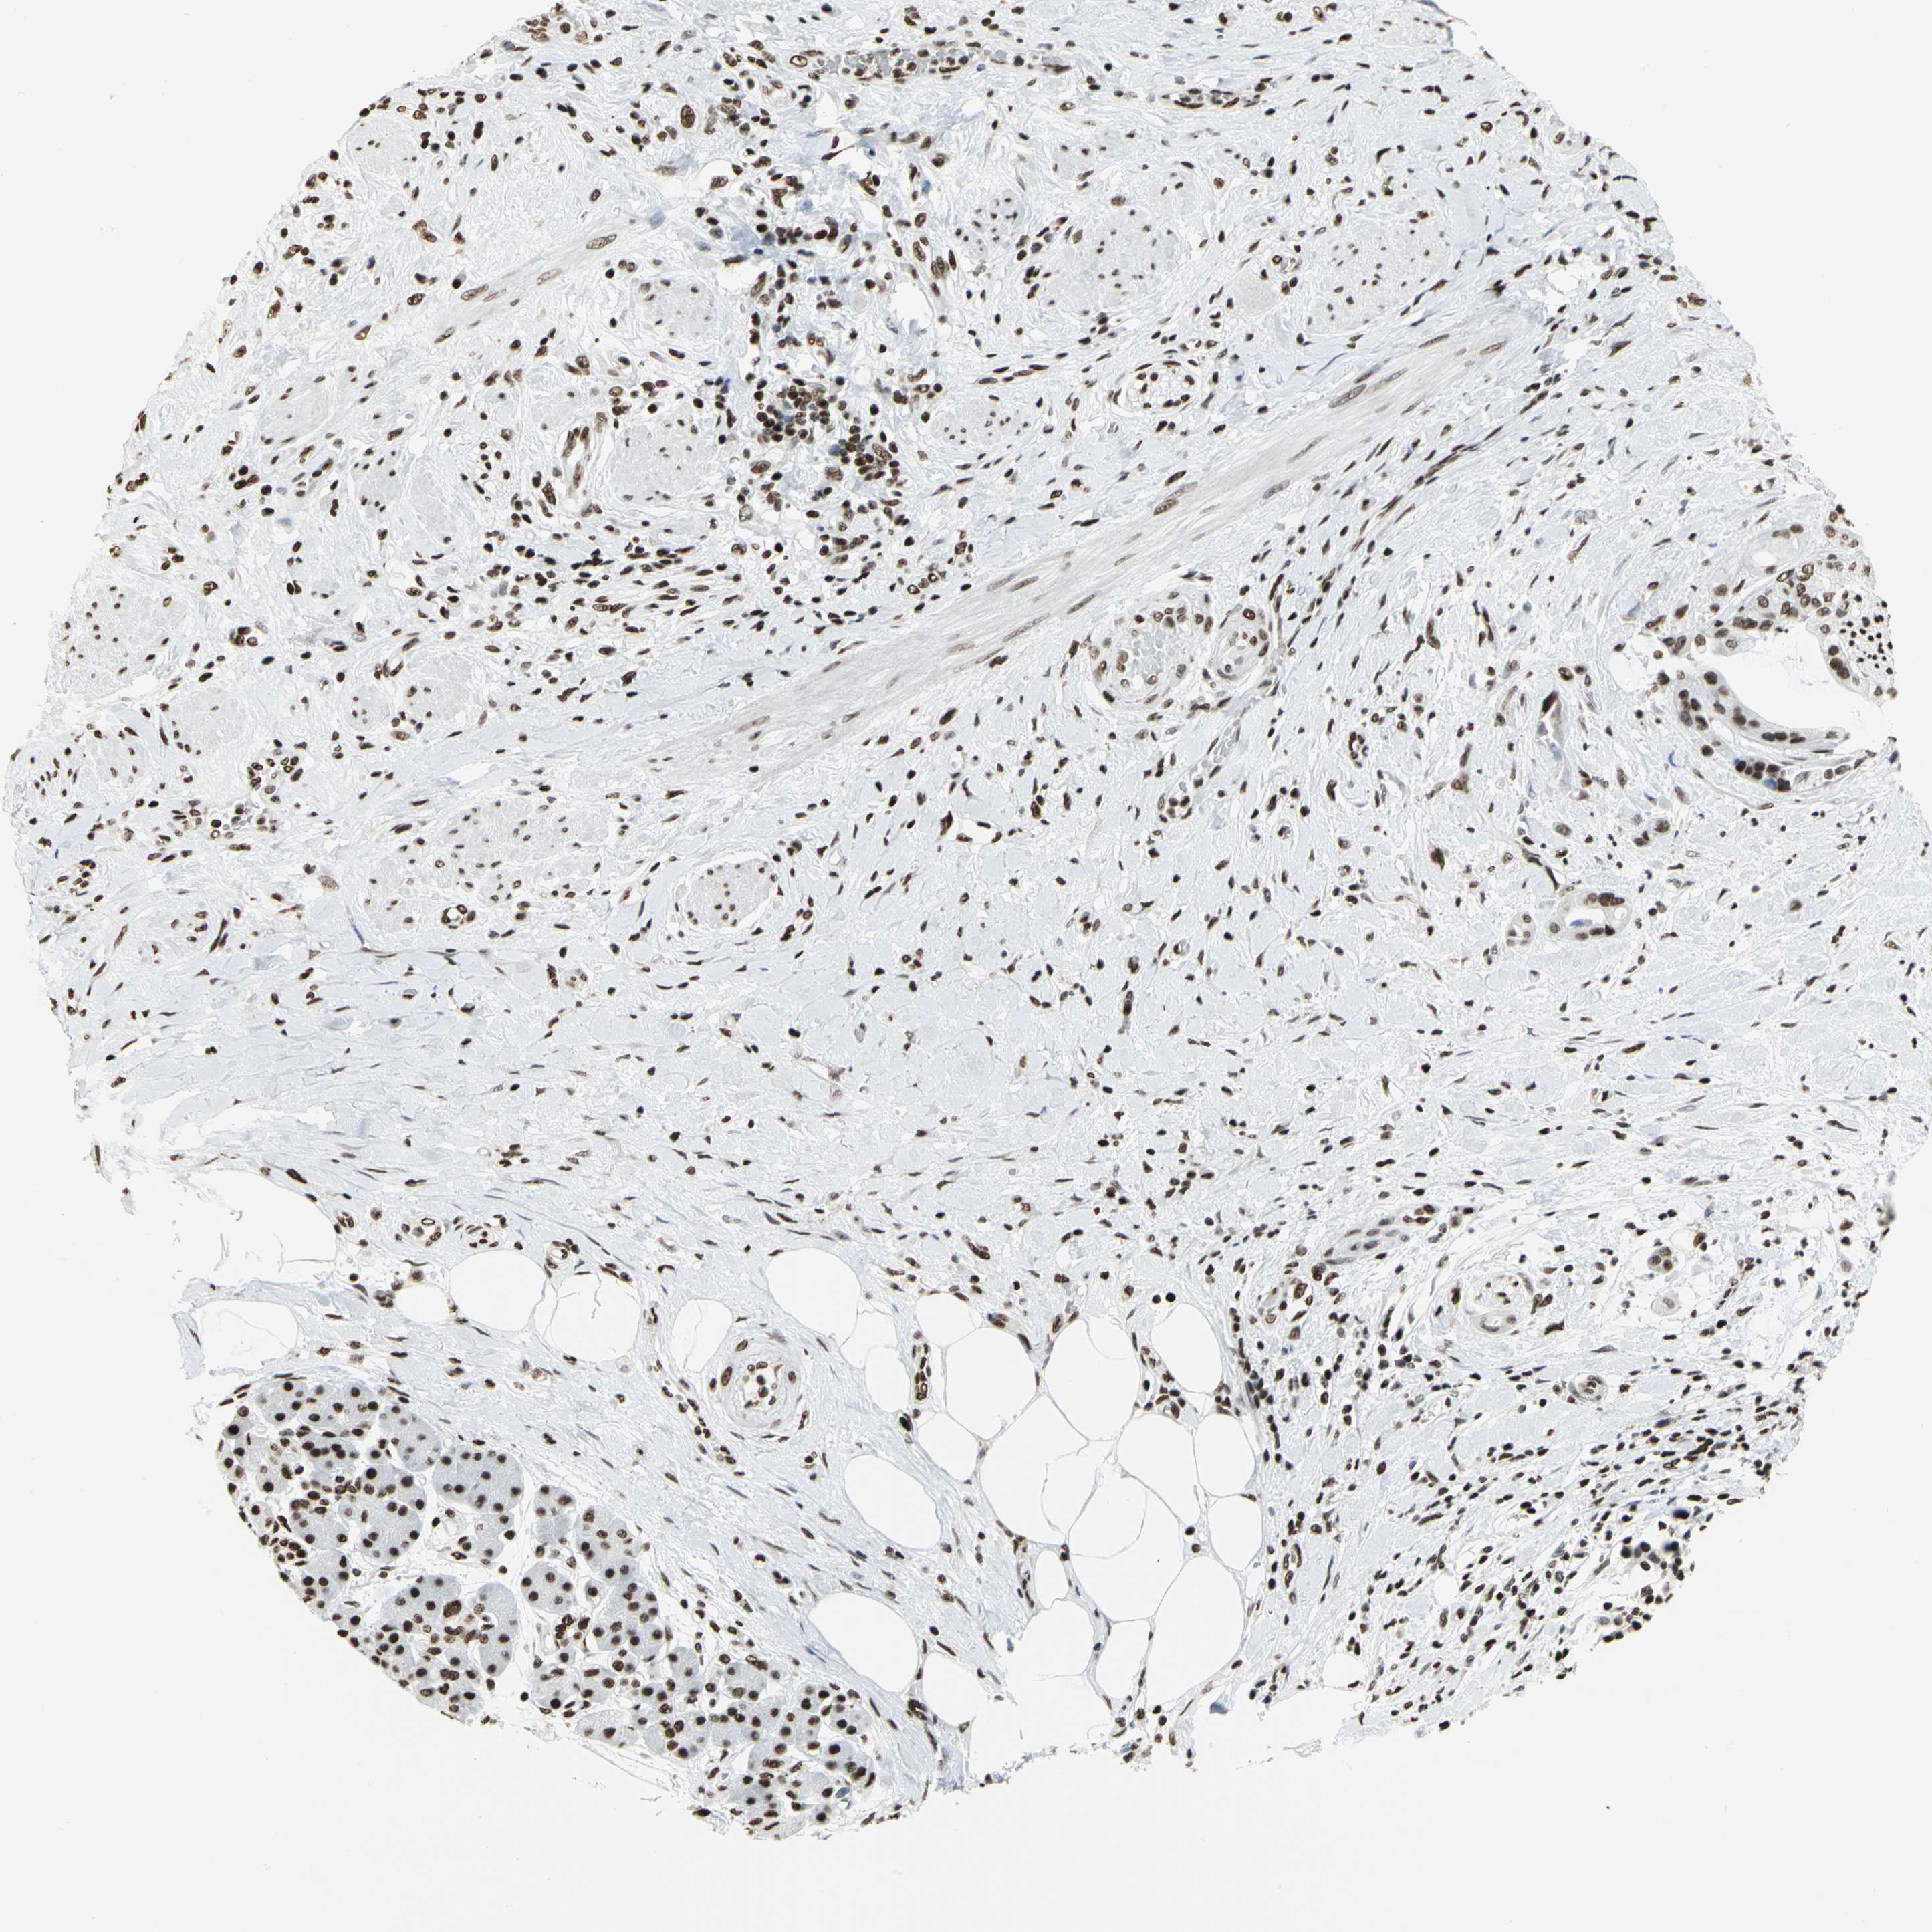

PANCREATIC CANCER - Protein expressioni

A mouse-over function shows sample information and annotation data. Click on an image to view it in a full screen mode. Samples can be filtered based on level of antibody staining by selecting one or several of the following categories: high, medium, low and not detected. The assay and annotation is described here.

Note that samples used for immunohistochemistry by the Human Protein Atlas do not correspond to samples in the TCGA dataset.

Antibody stainingi

Antibody staining in the annotated cell types in the current human tissue is reported as not detected, low, medium, or high, based on conventional immunohistochemistry profiling in selected tissues. This score is based on the combination of the staining intensity and fraction of stained cells.

Each image is clickable and will lead to virtual microscopy that enables deeper exploration of all samples and also displays staining intensity scores, fraction scores and subcellular localization as well as patient and tissue information for each sample.

Antibody HPA003506

Antibody CAB005873

Staining

High

Medium

Low

Not detected

Intensity

Strong

Moderate

Weak

Negative

Quantity

>75%

75%-25%

<25%

None

Location

Nuclear

Cytoplasmic/membranous

Cytoplasmic/membranous,nuclear

Adenocarcinoma, NOS

Adenocarcinoma, metastatic, NOS